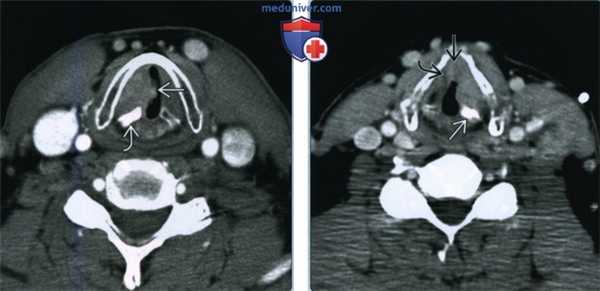

(Слева) При аксиальной КТ с КУ визуализируется большая опухоль (ПКР) правой ложной голосовой складки. Щитовидный хрящ склерозирован, однако это не позволяет сделать достоверный вывод о его опухолевой инвазии. Опухоль прорастает через внутреннюю и наружную поверхность щитовидного хряща и обнаруживается спереди. Стадия опухоли: Т4а.

(Справа) При аксиальной КТ с КУ визуализируется большая опухоль (плоскоклеточный рак) преддверия гортани (Т4а), полностью перекрывающая дыхательные пути, прорастающая через щитовидный хрящ, распространяющаяся за пределы гортани (в ремнеобразные мышцы) в виде массивного объемного образования. Обратите внимание, что опухоль близко прилежит к сонному влагалищу.1. Общие характеристики: